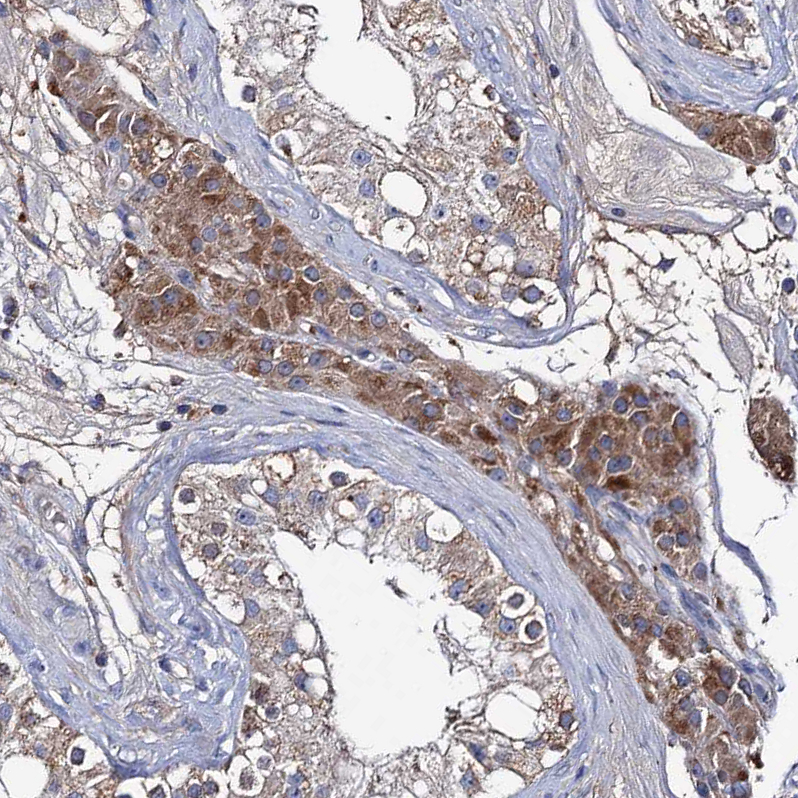

Immunohistochemical staining of human testis shows moderate granular cytoplasmic positivity in Leydig cells.